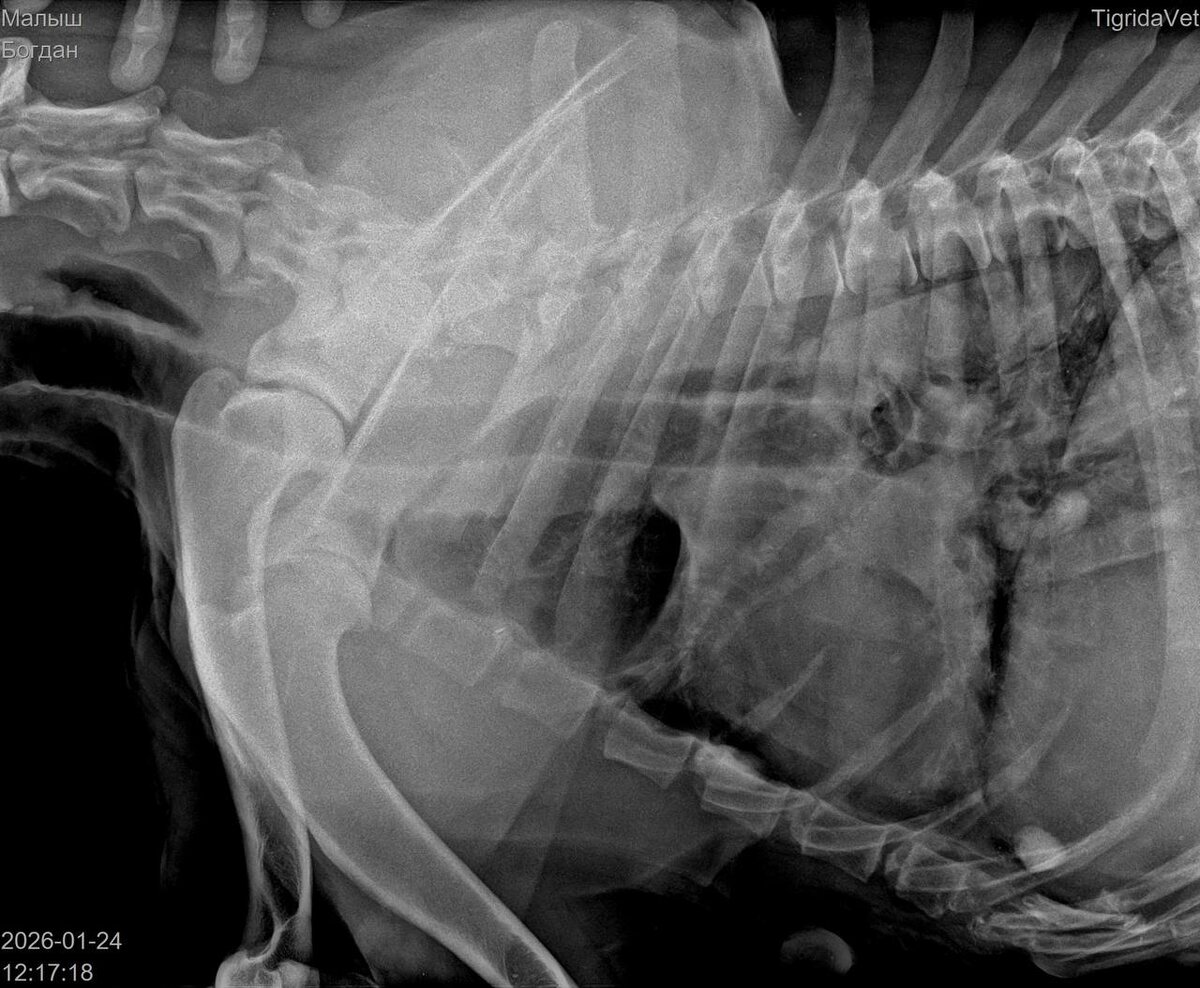

Был сделан рентген в нескольких проекциях.

Травмы были несовместимы с жизнью. Либо животное должно было быть помещено в стационар в какую-то московскую клинику, где его кормили бы через зонд. Самостоятельно он питаться не мог.

Со слов врача, внутри было множество пуль. По его подсчётам уже их видно было 9. А возможно и больше.